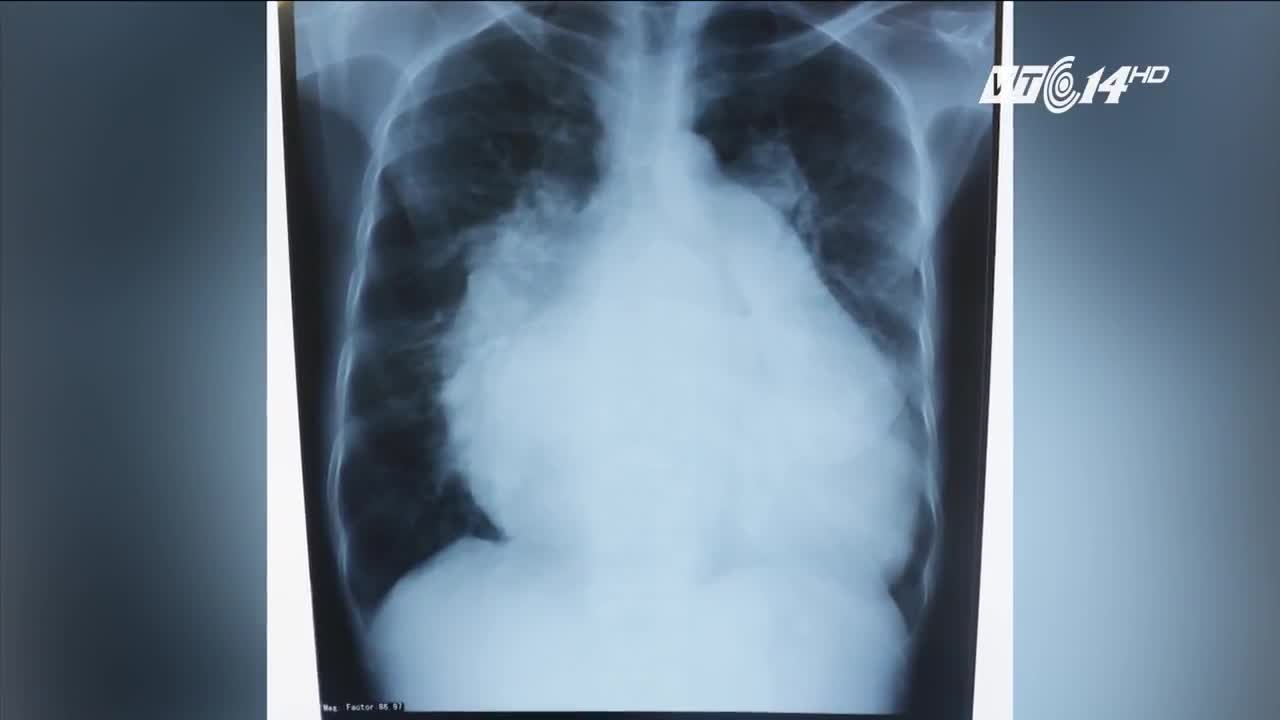

Sau nhiều năm khổ sở, nữ bệnh nhân này đã được phẫu thuật miễn phí.